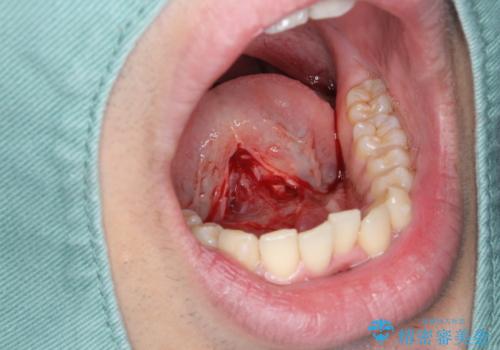

滑舌の改善 舌小帯の形成術

- 舌が動かしづらく、滑舌の改善を希望され来院されました。

舌小帯の形成術を即日で行い、1週間後に抜糸を行います。滑舌の改善を実感され、喜んでいただくことができました.

舌小帯の形成術は約10分程度で終了する小手術です。